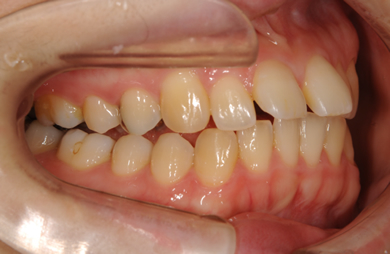

| 性別/年齢 | 女性 / 31歳 | ||||||||||||||||||||||||||||||||

| 主訴 | 歯並びを綺麗にしたい。 | ||||||||||||||||||||||||||||||||

| 治療方針 | 口元がきれいなので、なるべく横顔を変えないように歯を抜かずに治療を行う。しかし、下顎がだいぶ前に出ていて、上下の顎の前後的な位置のずれが大きいため、下顎にはインプラントアンカーを用いて、下の歯を本来の位置まで後ろに引っ張って治す。 | ||||||||||||||||||||||||||||||||

| 治療内容 | 唇側矯正(シルバー)、保定装置、矯正用スピードインプラント2本 | ||||||||||||||||||||||||||||||||

| 治療期間 | 1年5ヶ月 |